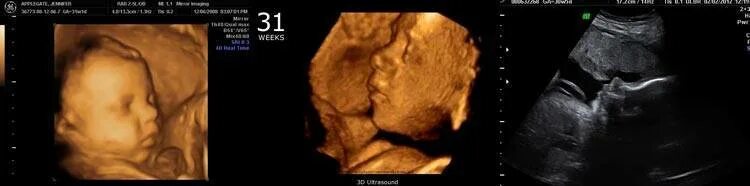

Плод на 31 неделе беременности. ребенок в животе 31 неделя.Эмбрион 31 неделя беременности. малыш на 31 неделе беременности.Плод на 31 неделе беременности. эмбрион 31 неделя беременности. малыш в утробе 31 неделя беременности.Малыш на 31 неделе беременности. малыш в животике 28 недель. малыш в утробе 31 неделя.Младенец в утробе. малыш в утробе 31 неделя. ребёнок на 31 неделе беременности.Плод на 31 неделе беременности. ребёнок на 31 неделе беременности. малыш в утробе 31 неделя. младенец на 31 неделе беременности.Плод на 31 неделе беременности. 30-31 неделя беременности. эмбрион 31 неделя беременности. 31 акушерская неделя беременности.Малыш на 31 неделе беременности.Плод на 31 неделе беременности. расположение ребёнка в утробе матери на 29 неделе.30-31 неделя беременности. ребёнок в матке на 31 неделе. плод на 31 неделе беременности.Плод ребенка. ребёнок на 31 неделе беременности.Плод на 31 неделе беременности. малыш в утробе 31 неделя беременности. ребёнок в 30 недель беременности. ркбкеок на 30 неделе беременности.Плод на 31 неделе беременности. малыш на 31 неделе беременности.Эмбрион леннарт нильсон. плод на 31 неделе беременности. леннарт нильсон фотографии.Малыш на 31 неделе беременности. ребёнок на 31 неделе беременности в животе. малыш в утробе 31 неделя беременности.Узи плода 31 неделя беременности. узи беременности 30-31 неделя. узи 31 неделя беременности мальчик. 31 неделя беременности узи фото.Узи на 33 неделе беременности мальчик. снимок узи на 31 неделе беременности. узи 31 неделя беременности мальчик.Плод на 31 неделе беременности. расположение ребенка в утробе матери на 30 недели беременности. расположение плода на 31 неделе беременности. малыш в утробе матери 31 неделя беременности.Узи плода 31 неделя беременности. 31 неделя беременности фото узи ребенка. снимок узи на 31 неделе беременности. узи беременности 30-31 неделя.Плод на 31 неделе беременности. 31 неделя беременности фото плода. плод ребенка в 31 неделю беременности. малыш на 31 неделе беременности.Плод на 30 неделе беременности. плод ребенка на 30 неделе беременности. ребёнок в 30 недель беременности. 31 неделя беременности фото плода.31 неделя беременности как выглядит31 неделя беременности фото плода на узи. 3д узи 31 неделя беременности девочка. 3д узи на 31 неделе беременности.Узи 31 неделя беременности. узи плода 31 неделя беременности. 31 неделя беременности узи фото. эмбрион на 30 неделе беременности узи.Ребёнок на 31 неделе беременности. узи хомиладорлик.Узи ребенка на 31 неделе беременности. 32 недели беременности фото плода на узи. 31 неделя беременности фото плода на узи. снимок узи 32 недели беременности.Малыш в животике на 32 неделе. ребёнок на 31 неделе беременности. 31-32 неделя беременности.Живот на 31 неделе беременности. животик на 31 неделе беременности. ребёнок на 31 неделе беременности в животе.Живот на 31 неделе. животик на 31 неделе беременности. беременный живот на 31 неделе.Беременность 29 недель положение плода. ребенок в животе на 25 неделе. плод на 32 неделе беременности. матка на 21 неделе беременности.Малыш в утробе 32 неделе беременности. плод 31-32 недели беременности. ребёнок на 32 неделе беременности в утробе. плод в 32 недели беременности в животе.Живот на 31 неделе. живот на 30-31 неделе. живот на 31 неделе беременности животик.Ребёнок на 24 неделе беременности. оебнок на 24 неделе беременности. новорожденный ребенок на 24 неделе беременности.Ребёнок 30 неделя беременности в утробе. малыш в утробе 31 неделя беременности.Ребенок в 32-33 недели беременности. плод на 33 неделе беременности. ребенок на 33 неделе беременности. малыш на 33 неделе беременности.Ребёнок в 34 недели беременности в утробе. 32 недели беременности фото плода. малыш в утробе 32 неделе беременности. ребёнок в 32 недели беременности в животе.Ребёнок на 32 неделе беременности. новорожденный в 35 недель.Малыш на 31 неделе беременности. новорожденный ребенок 31 неделя. рождение ребенка на 31 недели беременности.31 неделя беременности как выглядитПлод на 34 неделе беременности картинки. 34 неделя беременности фото плода. 34 эмбриональная неделя беременности. плод ребенка в 34 недели беременности.